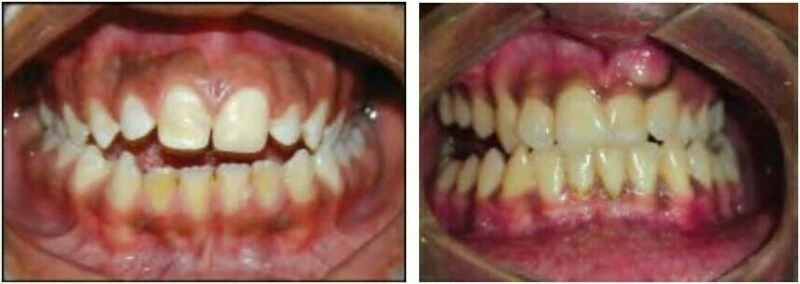

2) KHÔNG CÂN XỨNG GIỮA CÁC CUNG HÀM

Kiểu sai khớp cắn này đặc trưng bởi sự tương quan bất thường giữa các răng và các nhóm răng của một cung hàm với cung hàm còn lại. Tình trạng không cân xứng giữa các cung răng có thể xảy ra theo ba mặt phẳng trong không gian – mặt phẳng đứng dọc, mặt phẳng đứng ngang hoặc mặt phẳng ngang

2.2 SAI KHỚP CẮN THEO MẶT PHẲNG ĐỨNG NGANG

Trường hợp này có thể chia làm hai phân loại tùy thuộc vào độ phủ theo chiều dọc của các răng giữa hai hàm.

Cắn sâu

Với loại này, độ cắn phủ theo chiều dọc giữa răng hàm trên và răng hàm dưới lớn hơn so với bình thường.

Cắn hở

Với loại này thì không có độ phủ hoặc chỉ có một khoảng trống giữa các răng hàm trên và hàm dưới khi bệnh nhân cắn lại ở khớp cắn trung tâm. Một trường hợp cắn hở có thể gặp ở răng trước hoặc răng sau.

2.3 SAI KHỚP CẮN THEO MẶT PHẲNG NGANG

Trường hợp này bao gồm nhiều kiểu cắn chéo khác nhau. Thông thường các răng hàm trên nằm về phía ngoài so với các răng hàm dưới, nhưng đôi khi do cung răng hẹp hoặc vì một số lý do khác mà tương quan này bị xáo trộn. Chẳng hạn một hoặc nhiều răng hàm trên nằm về phía trong so với các răng hàm dưới, tình trạng này khác nhau về mức độ, vị trí và số lượng răng liên quan.